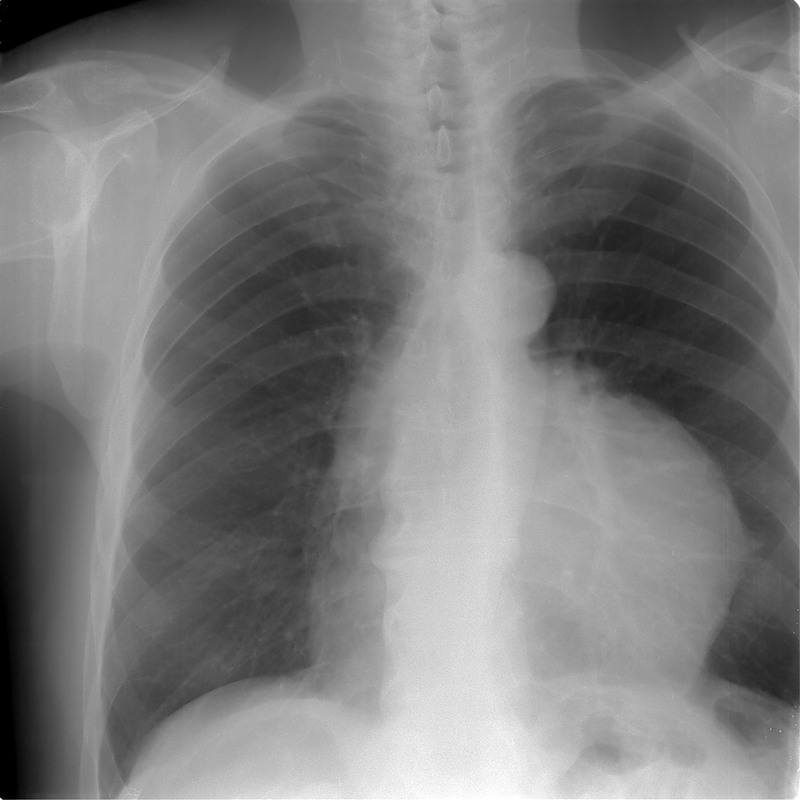

Рентгенограмма при тимоме